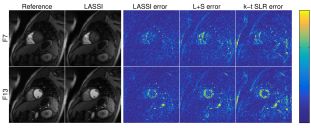

Fig. 3 shows the NRMSE values computed between each reconstructed and reference frame for the LASSI, L+S, and k-t SLR outputs for two datasets. The proposed LASSI scheme clearly outperforms the previous L+S and k-t SLR methods across frames (time). Fig. 4 shows the LASSI reconstructions of some representative frames (the supplement shows more such reconstructions) for each dataset in Tables I-III. The reconstructed frames are visually similar to the reference frames (fully sampled reconstructions) shown. Fig. 4 also shows the reconstruction error maps (i.e., the magnitude of the difference between the magnitudes of the reconstructed and reference frames) for LASSI, L+S, and k-t SLR for the representative frames of each dataset. The error maps for LASSI show fewer artifacts and smaller distortions than the other methods. Results included in the supplement show that LASSI recovers temporal () profiles in the dynamic data with greater fidelity than other methods.

IV-D A Study of Various LASSI Models and Methods